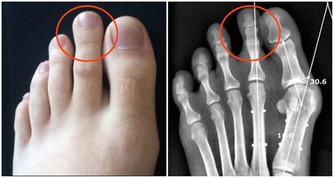

部分引起慢性便秘的病因危險性很大,如肛門損傷、腸梗阻、腸嵌塞或潰瘍、腸道惡性腫瘤等,此時最好及時到專科門診就診,以免延誤疾病診治。